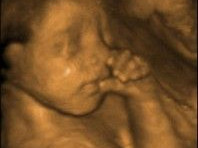

Nejlepší zobrazitelnost plodu je kolem 26. týdne těhotenství, kdy je plod už dostatečně velký a jsou patrné i velmi jemné detaily ve struktuře těla a zároveň je dostatečné množství plodové vody, která je nezbytná pro dosažení kvalitního zobrazení.

3D/4D ultrazvuk poskytuje unikátní možnost sledovat detailní trojrozměrné obrazy (3D) a dokonce i reálný pohyb jejich nenarozeného dítěte (4D). Díky této technologii mohou rodiče prozkoumat tvářičku, končetiny a orgány dítěte s neuvěřitelnou jasností a živostí.